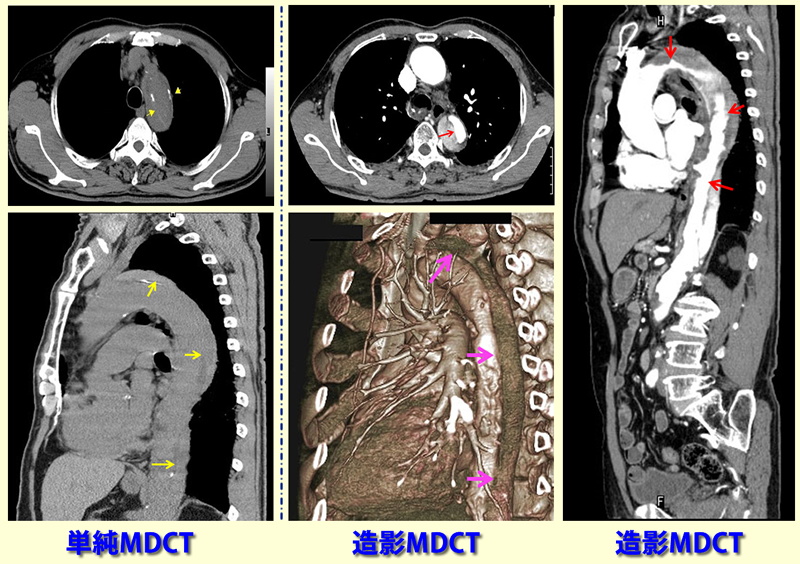

深夜、午前1時30分頃、胸背部痛が車運転中生じ、持続するため2時30分来院。胸腹部の単純CT検査(左側画像)で大動脈解離疑われ、造影CTで精査。中央、右側の造影MDCT検査で胸部から骨盤部までの大動脈解離と確診し、救急車で血管外科に搬送。 急性解離性大動脈瘤